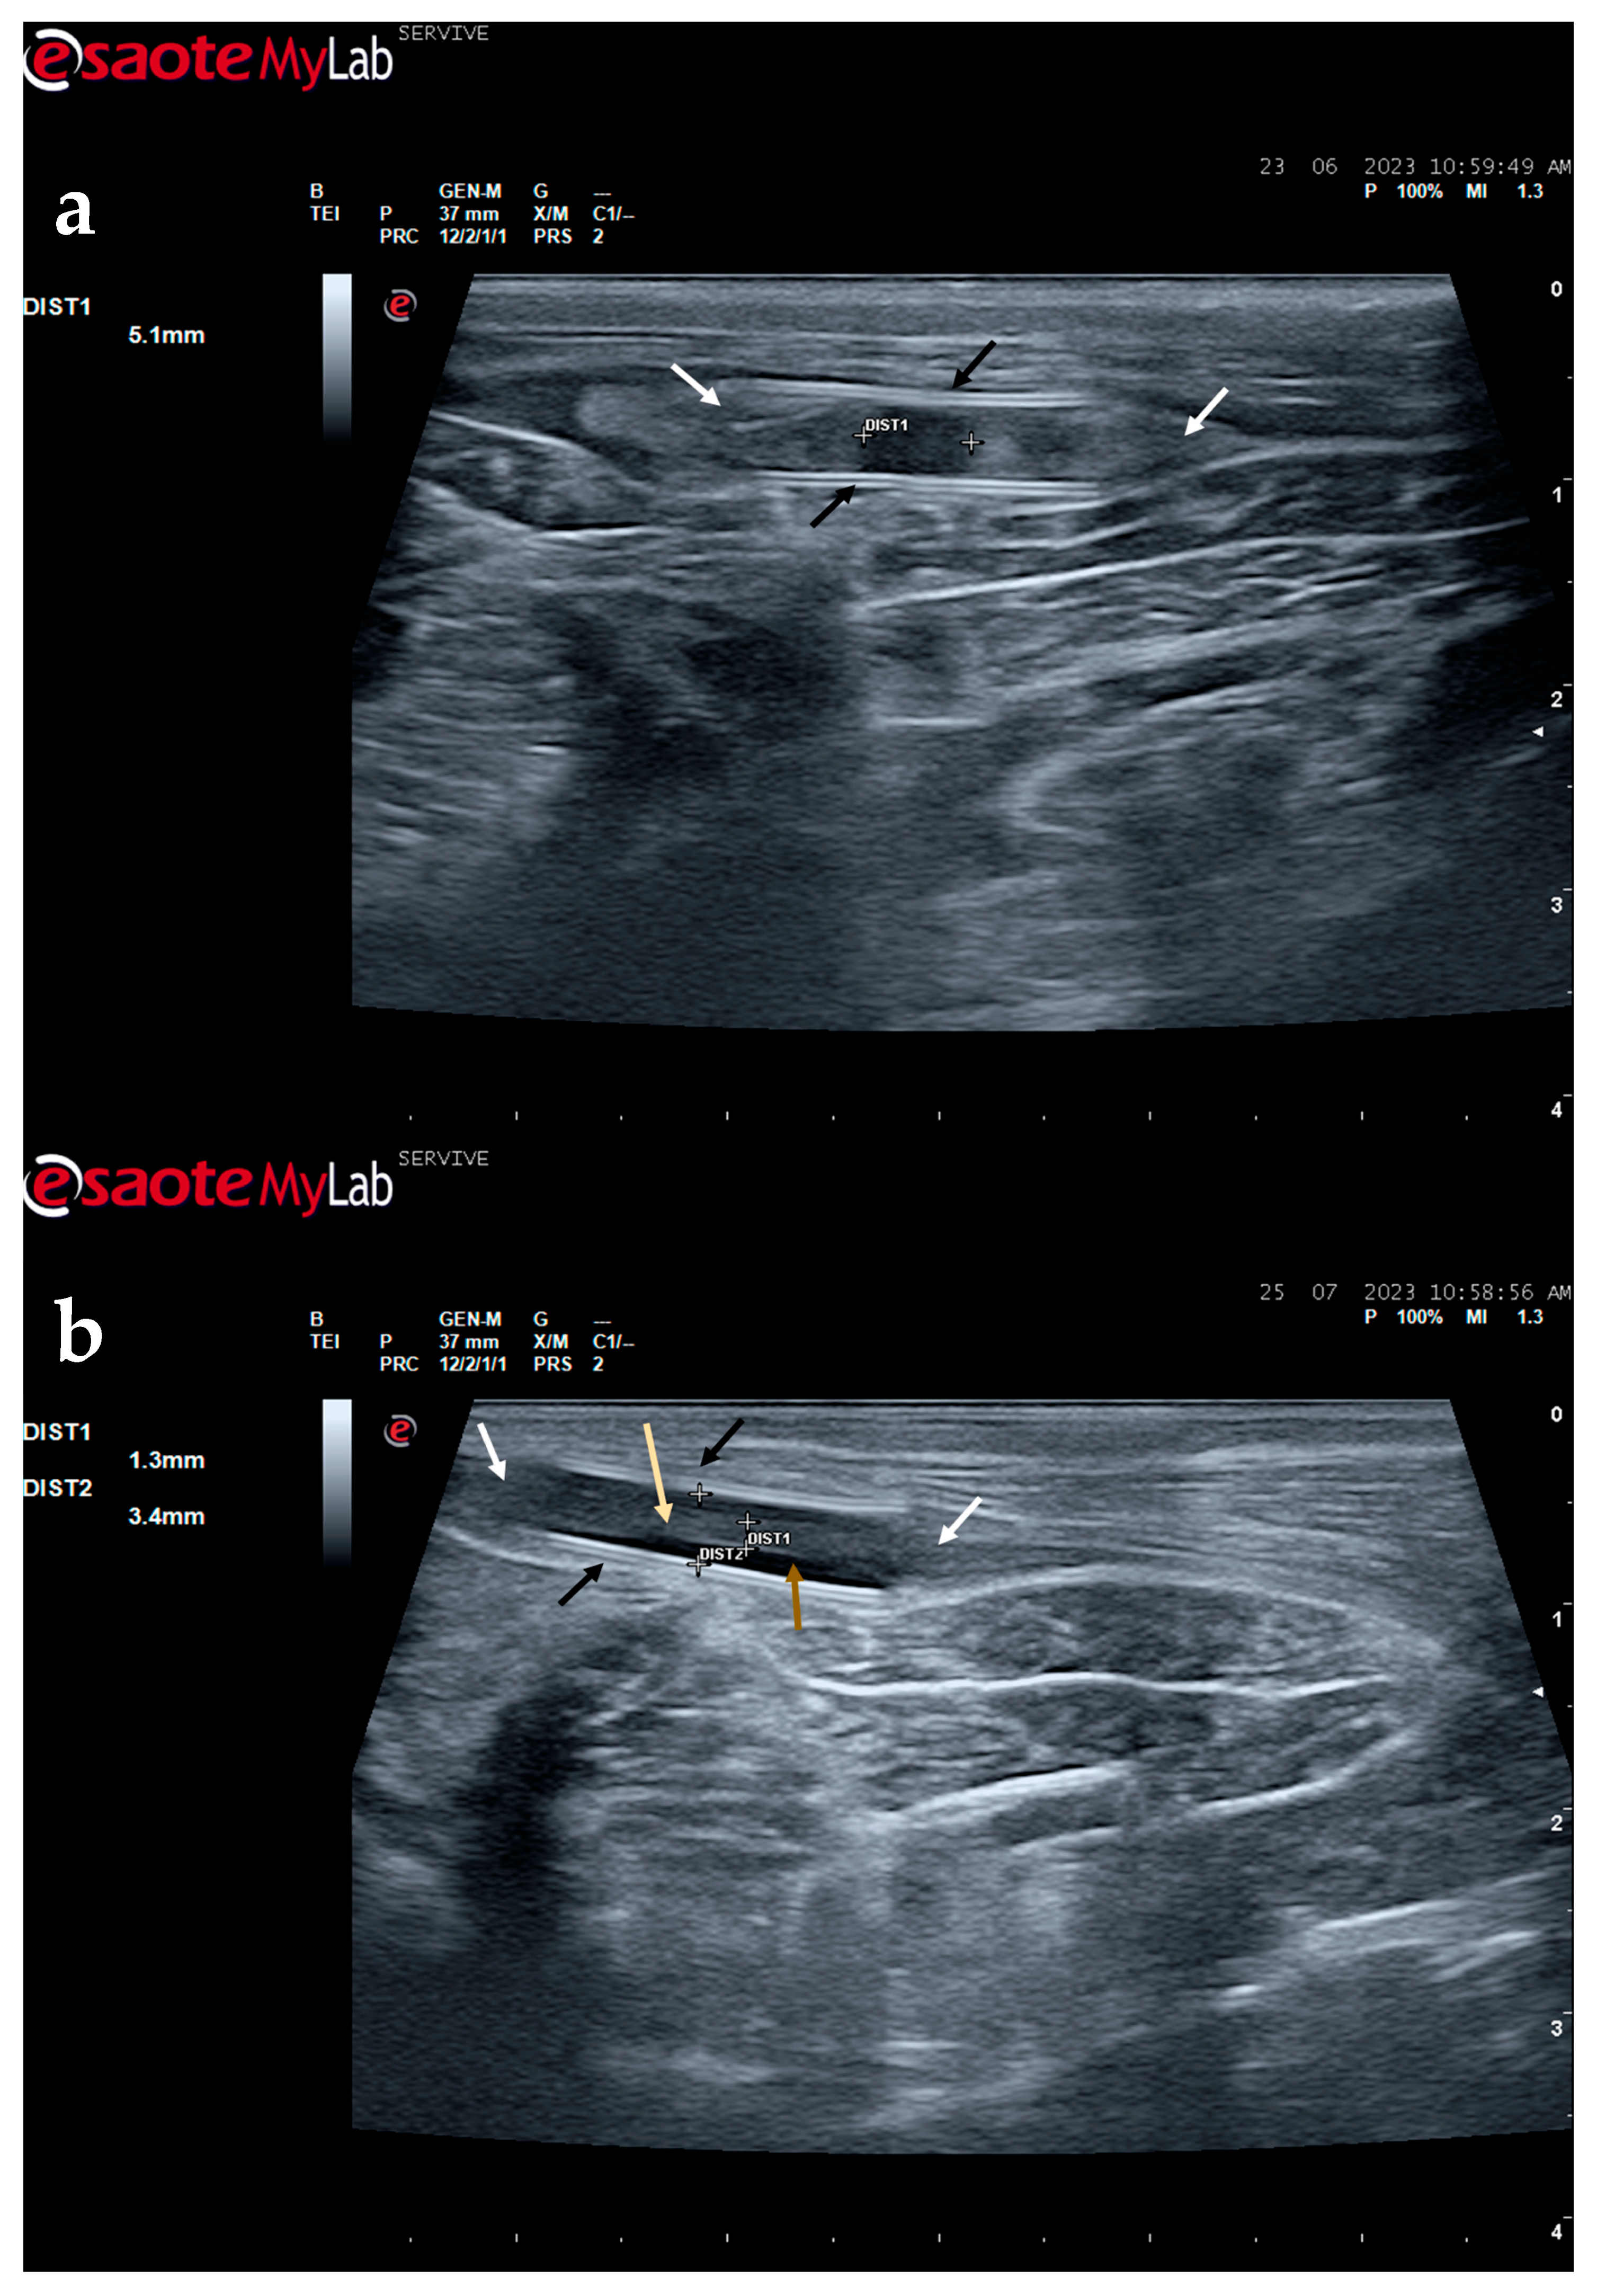

Figure 9.

Ultrasound image of the left peroneal nerve in a sheep subjected to a transection lesion followed by the application of a tube guide. (a) After 1 week, it is possible to observe the tube guide as a hyperechogenic tubular structure (black arrows) at the ends of which the ends of the transected nerve are inserted (white arrows). DIST1 represents the length of the gap left between the two nerve ends. (b) After 3 months, the tube continues to be perfectly visible (black arrows), and the nerve is introduced into its lumen (white arrows); but now, instead of the gap between the nerve tops, an anatomical continuity of the nerve is observed along the entire tubular lumen (beige arrow), indicating a nerve reconnection. In the center of the tubular lumen, a hypoechoic space not filled by nervous tissue is also observed (brown arrow), indicating that the regenerating nerve has not yet occupied all the available space inside the tube guide. DIST1 represents the nerve diameter, and DIST2 represents the inner diameter of the tube guide.